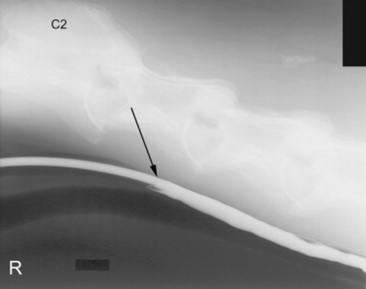

Radiography also allows for the use of contrast medium administration to further outline the alimentary tract as well as evaluate pharyngeal function and esophageal motility.12-14 In my opinion, first administering approximately 60 mL of barium sulfate paste or liquid orally via a 60-mL dosing syringe and obtaining radiographs of the laryngeal region and esophagus provide useful information about swallowing as well as large obstructions. If the barium liquid is identified dorsal to the soft palate, within the larynx or trachea, abnormal pharyngeal function is likely present.12 The barium paste will coat the pharynx and esophagus and is useful to identify any ulcerations or irregularities in the mucosal surface. After those procedures have been performed or if there is no evidence of an oropharyngeal dysphagia, then an esophagram is performed. This procedure is done using approximately 200 to 500 mL of barium sulfate liquid diluted 1:1 or 2:1 with water to bring the total volume to 500 to 1000 mL. This liquid is administered through a nasogastric tube or cuffed endotracheal tube placed within the cranial esophagus to the level of C2 to C3. If a cuff is available, the cuff can be inflated with approximately 10 mL of room air. A radiograph is then made to verify that the tube is not within the trachea, and when it has been confirmed that the tube is within the esophagus, the dose of barium is administered using a stomach pump. Toward the end of the dose, while still pumping the liquid, radiographs of the cranial, mid, and caudal esophagus are obtained (Fig. 32-9). The use of the pump provides distention of the esophagus to help identify strictures or irregularities in the esophageal wall.

image

Fig. 32-9 Standing lateral radiograph showing a normal esophagram using barium liquid. The arrow marks the region where the nasogastric tube ends. This is approximately at the level of C3.